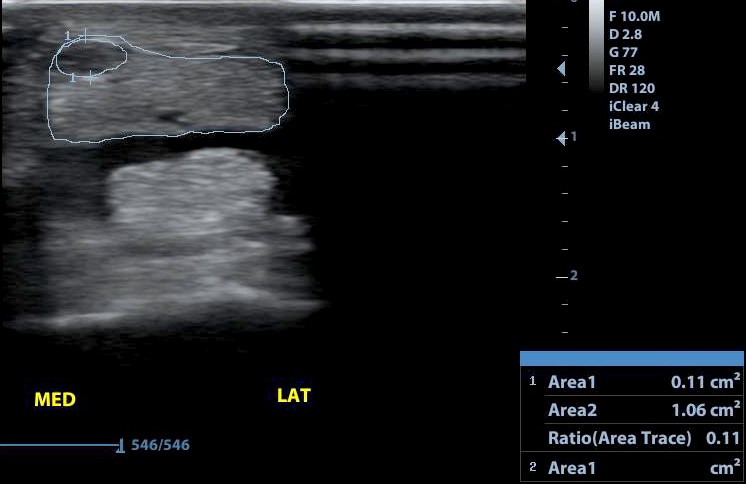

A mély ujjhajlító ín csüd alatti sérülése bejelölve. A mérés alapján a keresztmetszet 11 százalékát érintő sérülés.